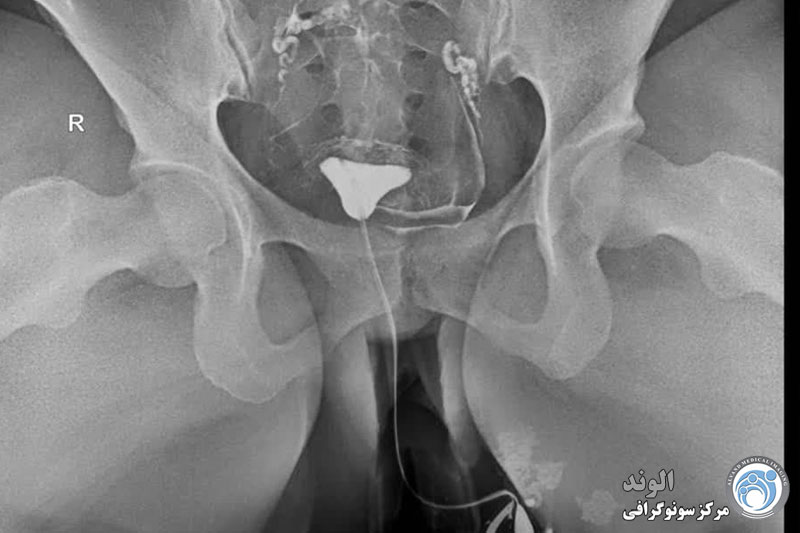

بیمار در وضعیت زنان (به پشت خوابیده، زانوهای خم شده و از هم باز)، زیر دستگاه اشعه ایکس قرار می گیرد. پزشک یک اسپکولوم را وارد واژن میکند، سپس یک کانولا را در دهانه رحم قرار میدهد که از طریق آن یک ماده حاجب تزریق میکند. این به داخل رحم و لوله های فالوپ گسترش می یابد. اشعه ایکس برای مشاهده پیشرفت خوب محصول و تجسم اندام ها گرفته می شود.

هیستروسالپنگوگرافی توسط رادیولوژیست انجام می شود. معاینه بدون بیهوشی انجام می شود. بیمار در موقعیت "زنان و زایمان" مستقر می شود. پزشک اسپکولوم را قرار می دهد، دهانه رحم را ضد عفونی می کند و سپس یک پروب را با روش طبیعی وارد رحم می کند. او به تدریج ماده حاجب را تزریق می کند. به طور معمول، ماده حاجب به تدریج رحم و لوله های فالوپ را کدر می کند تا زمانی که به حفره صفاقی منتقل شود.

چندین عکس رنگی رحم قبل، حین و بعد از تزریق محصول گرفته می شود و این در موقعیت های مختلف:

اشعه ایکس بدون آماده سازی (جستجو برای کلسیفیکاسیون لگن)؛

اشعه ایکس پر شدن ضعیف (پولیپ ها یا فیبروم های زیر مخاطی را برجسته می کند).

اشعه ایکس پر شدن لوله (ارزیابی وضعیت مخاط لوله).

عکس پروفایل (ارزیابی موقعیت رحم و مسیر لوله های فالوپ)؛

اشعه ایکس دیررس (بررسی گردش خون صفاقی، جستجو برای چسبندگی لگن).